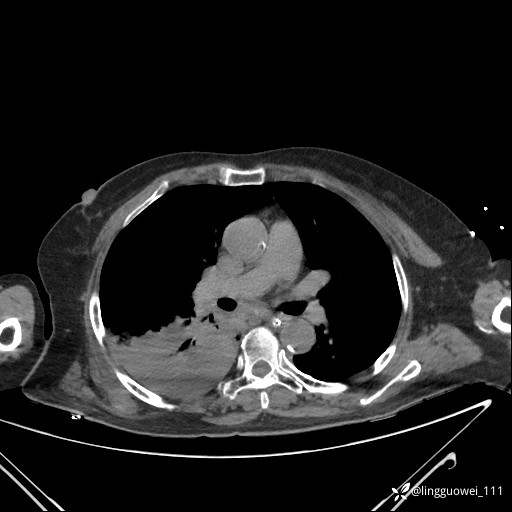

CT平扫:

20小时后,行胸部增强检查,病灶范围较前增大